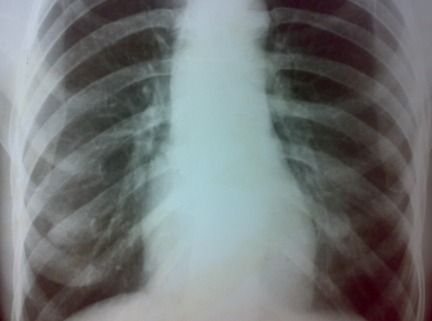

CT 및 PET 스캔:

흉부 및 복부 CT 스캔과 PET 스캔을 통해 암의 전이 여부를 확인합니다. 이 검사는 식도암이 주변 조직으로 전이되었는지를 평가하는 데 중요합니다.